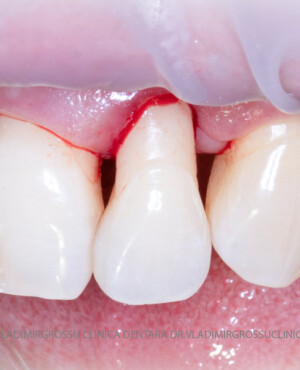

Adiția de gingie (gingivoplastia)

Aditia gingivală este o procedură chirurgicală ce corectează diverse probleme estetice și funcționale, cum ar fi recesiunea gingivală. În implantologia modernă, aditia de țesut moale este utilizată aproape în fiecare intervenție de inserție a implantului dentar pentru a asigura un aspect estetic natural și o bună integrare a implantului în cavitatea bucală.